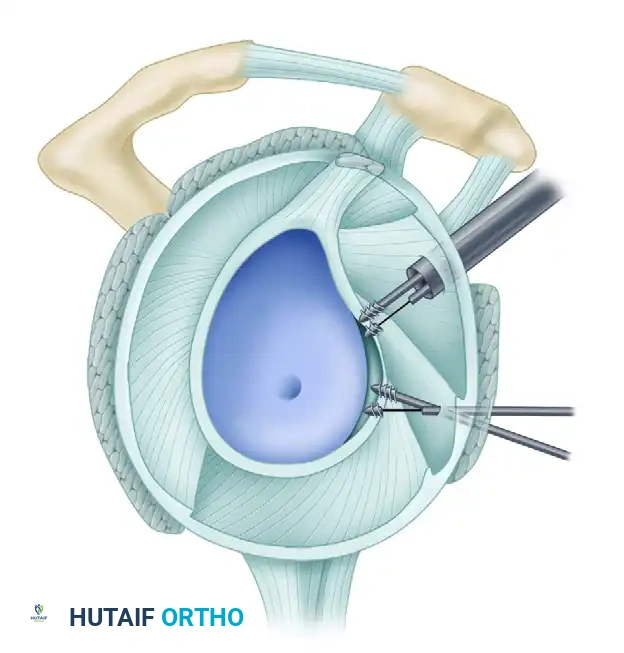

4. Suture Passing and Superior Advancement

To eliminate the drive-through sign and restore physiological tension, the capsule must be shifted superiorly and laterally.

- Retrieve the most inferior suture limb out of the posteroinferior cannula using a suture grasper.

- Use a Spectrum suture passer through the anterior cannula to take a substantial (1 cm) bite of the capsule and labrum inferior to the anchor site.

C, A 1-cm capsular bite taken with Spectrum suture passed distal to anchor.

- Shuttle the PDS relay suture out the posterior cannula, load the anchor suture, and pull it through the capsulolabral tissue.

- Retrieve the corresponding suture limb and tie a secure, low-profile sliding knot (e.g., SMC or Weston knot) backed up by alternating half-hitches.